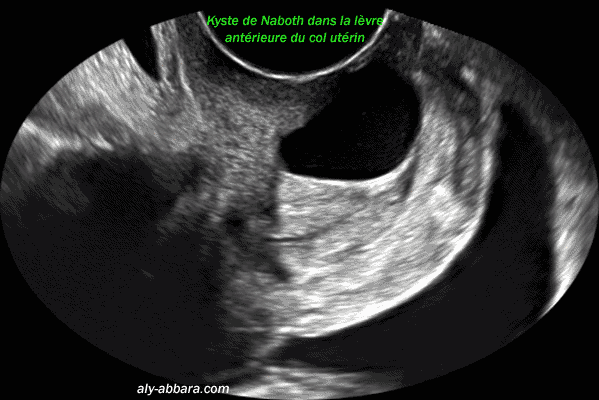

- Le kyste

de Naboth :

- Connu aussi sous le nom de follicule de Naboth, de kyste glandulaire

ou de kyste de rétention ; il se forme sous la surface épithélial

du col utérin lorsque l'orifice d'une crypte glandulaire endocervicale

est obstrué par l'épithélium cylindrique métaplasique,

l'épithélium glandulaire cylindrique reste actif à

l'intérieur de la crypte obstruée et il sécrète

du mucus qui dilate la glande et lui donne l'aspect kystique (ou folliculaire)

de taille variable

Ces kystes glandulaires rétentionnels sont visibles sur l'exocol,

mais paroi ils sont situés profondément dans le col

près du canal endocervical et invisibles à l'observation

du col par le spéculum ou le colposcope.